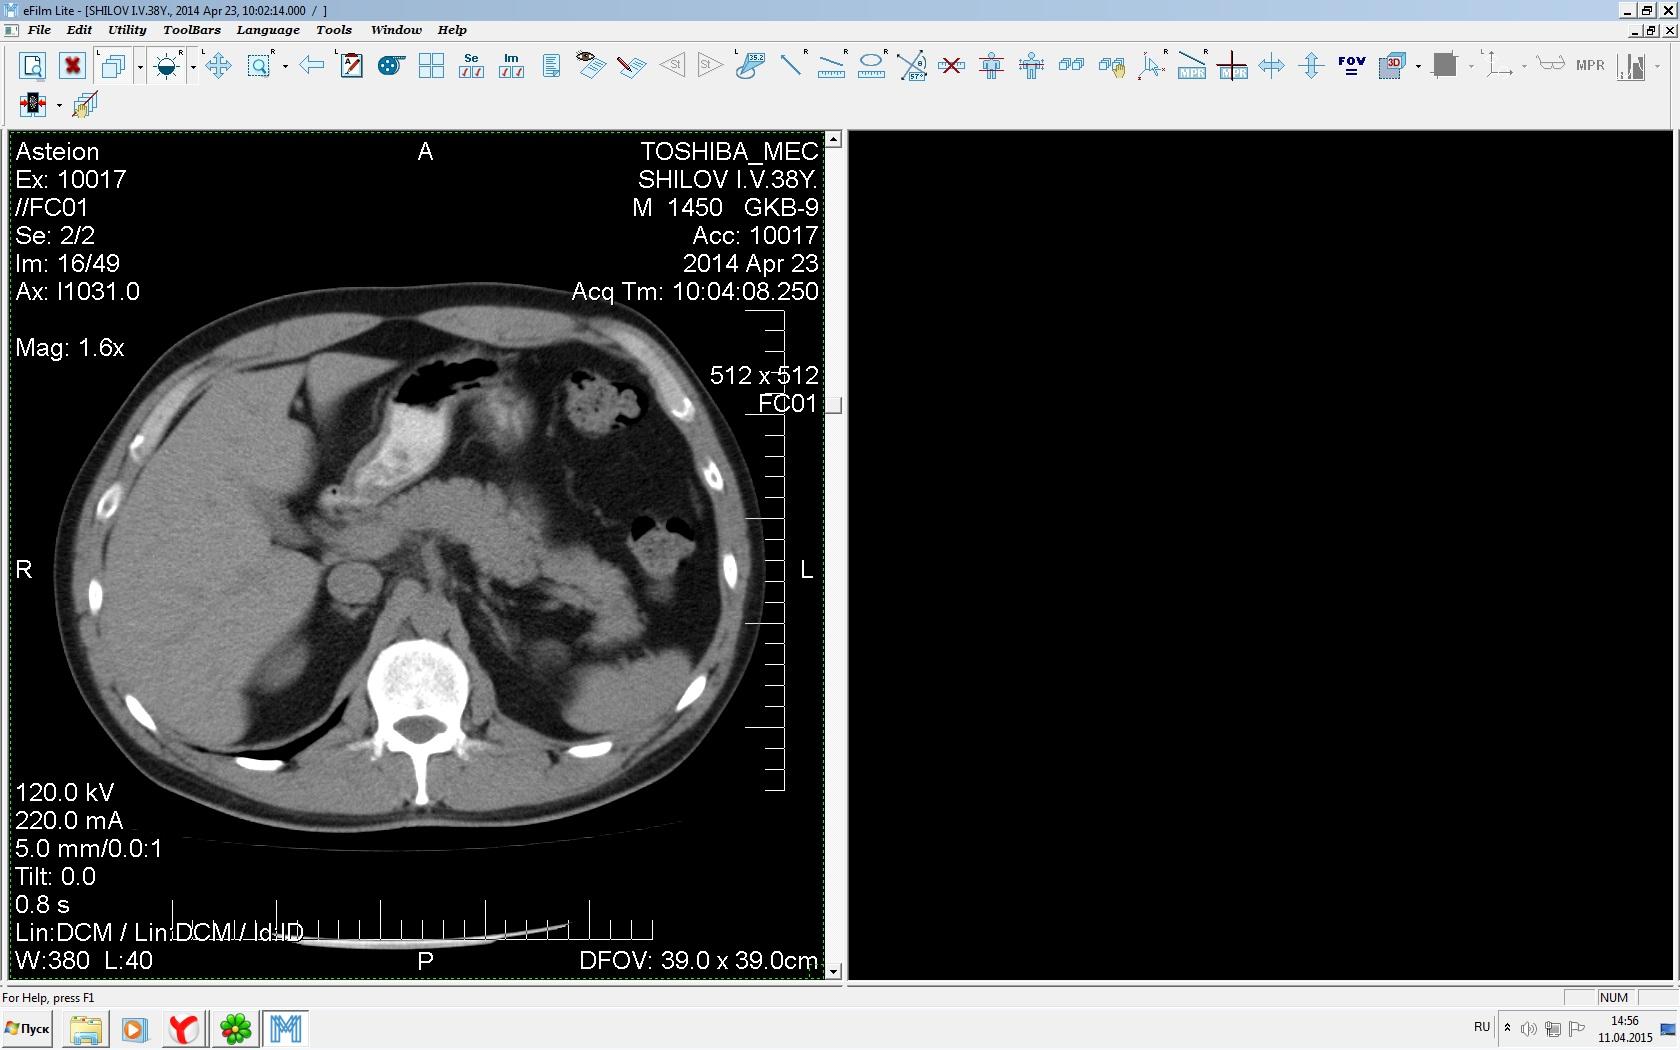

Здравствуйте. У меня киста левой почки. Из заключения: левая почка увеличена, деформирована за счёт наличия в среднем сегменте округлого жидкостного +6, +15 HU образования 66х53 мм, деформирует, поддавливает чаше-лоханочную систему. Сосудистые ножки структурные. В урологии мне сперва предложили лапароскопию, когда я лёг на операцию - изменили на полостную в связи со сложностью. Потом сказали что шансов вырезать кисту без почки практически нет. Даже если кисту удалить чудесным способом, то почка всё равно сложится и не будет работать. В итоге операцию отменили. Скажите, пожалуйста, есть ли современный метод удалить кисту и сохранить почку в моём случае? Томография почки в приложениях. Заранее благодарю.

Эту кисту можно просто пропунктировать, аспирировать и склерозировать - под местной анестезией. Ничего сверхестетственного не определяется по данным КТ. Можете написать мне на почту. aristova-tatyana@mail.ru